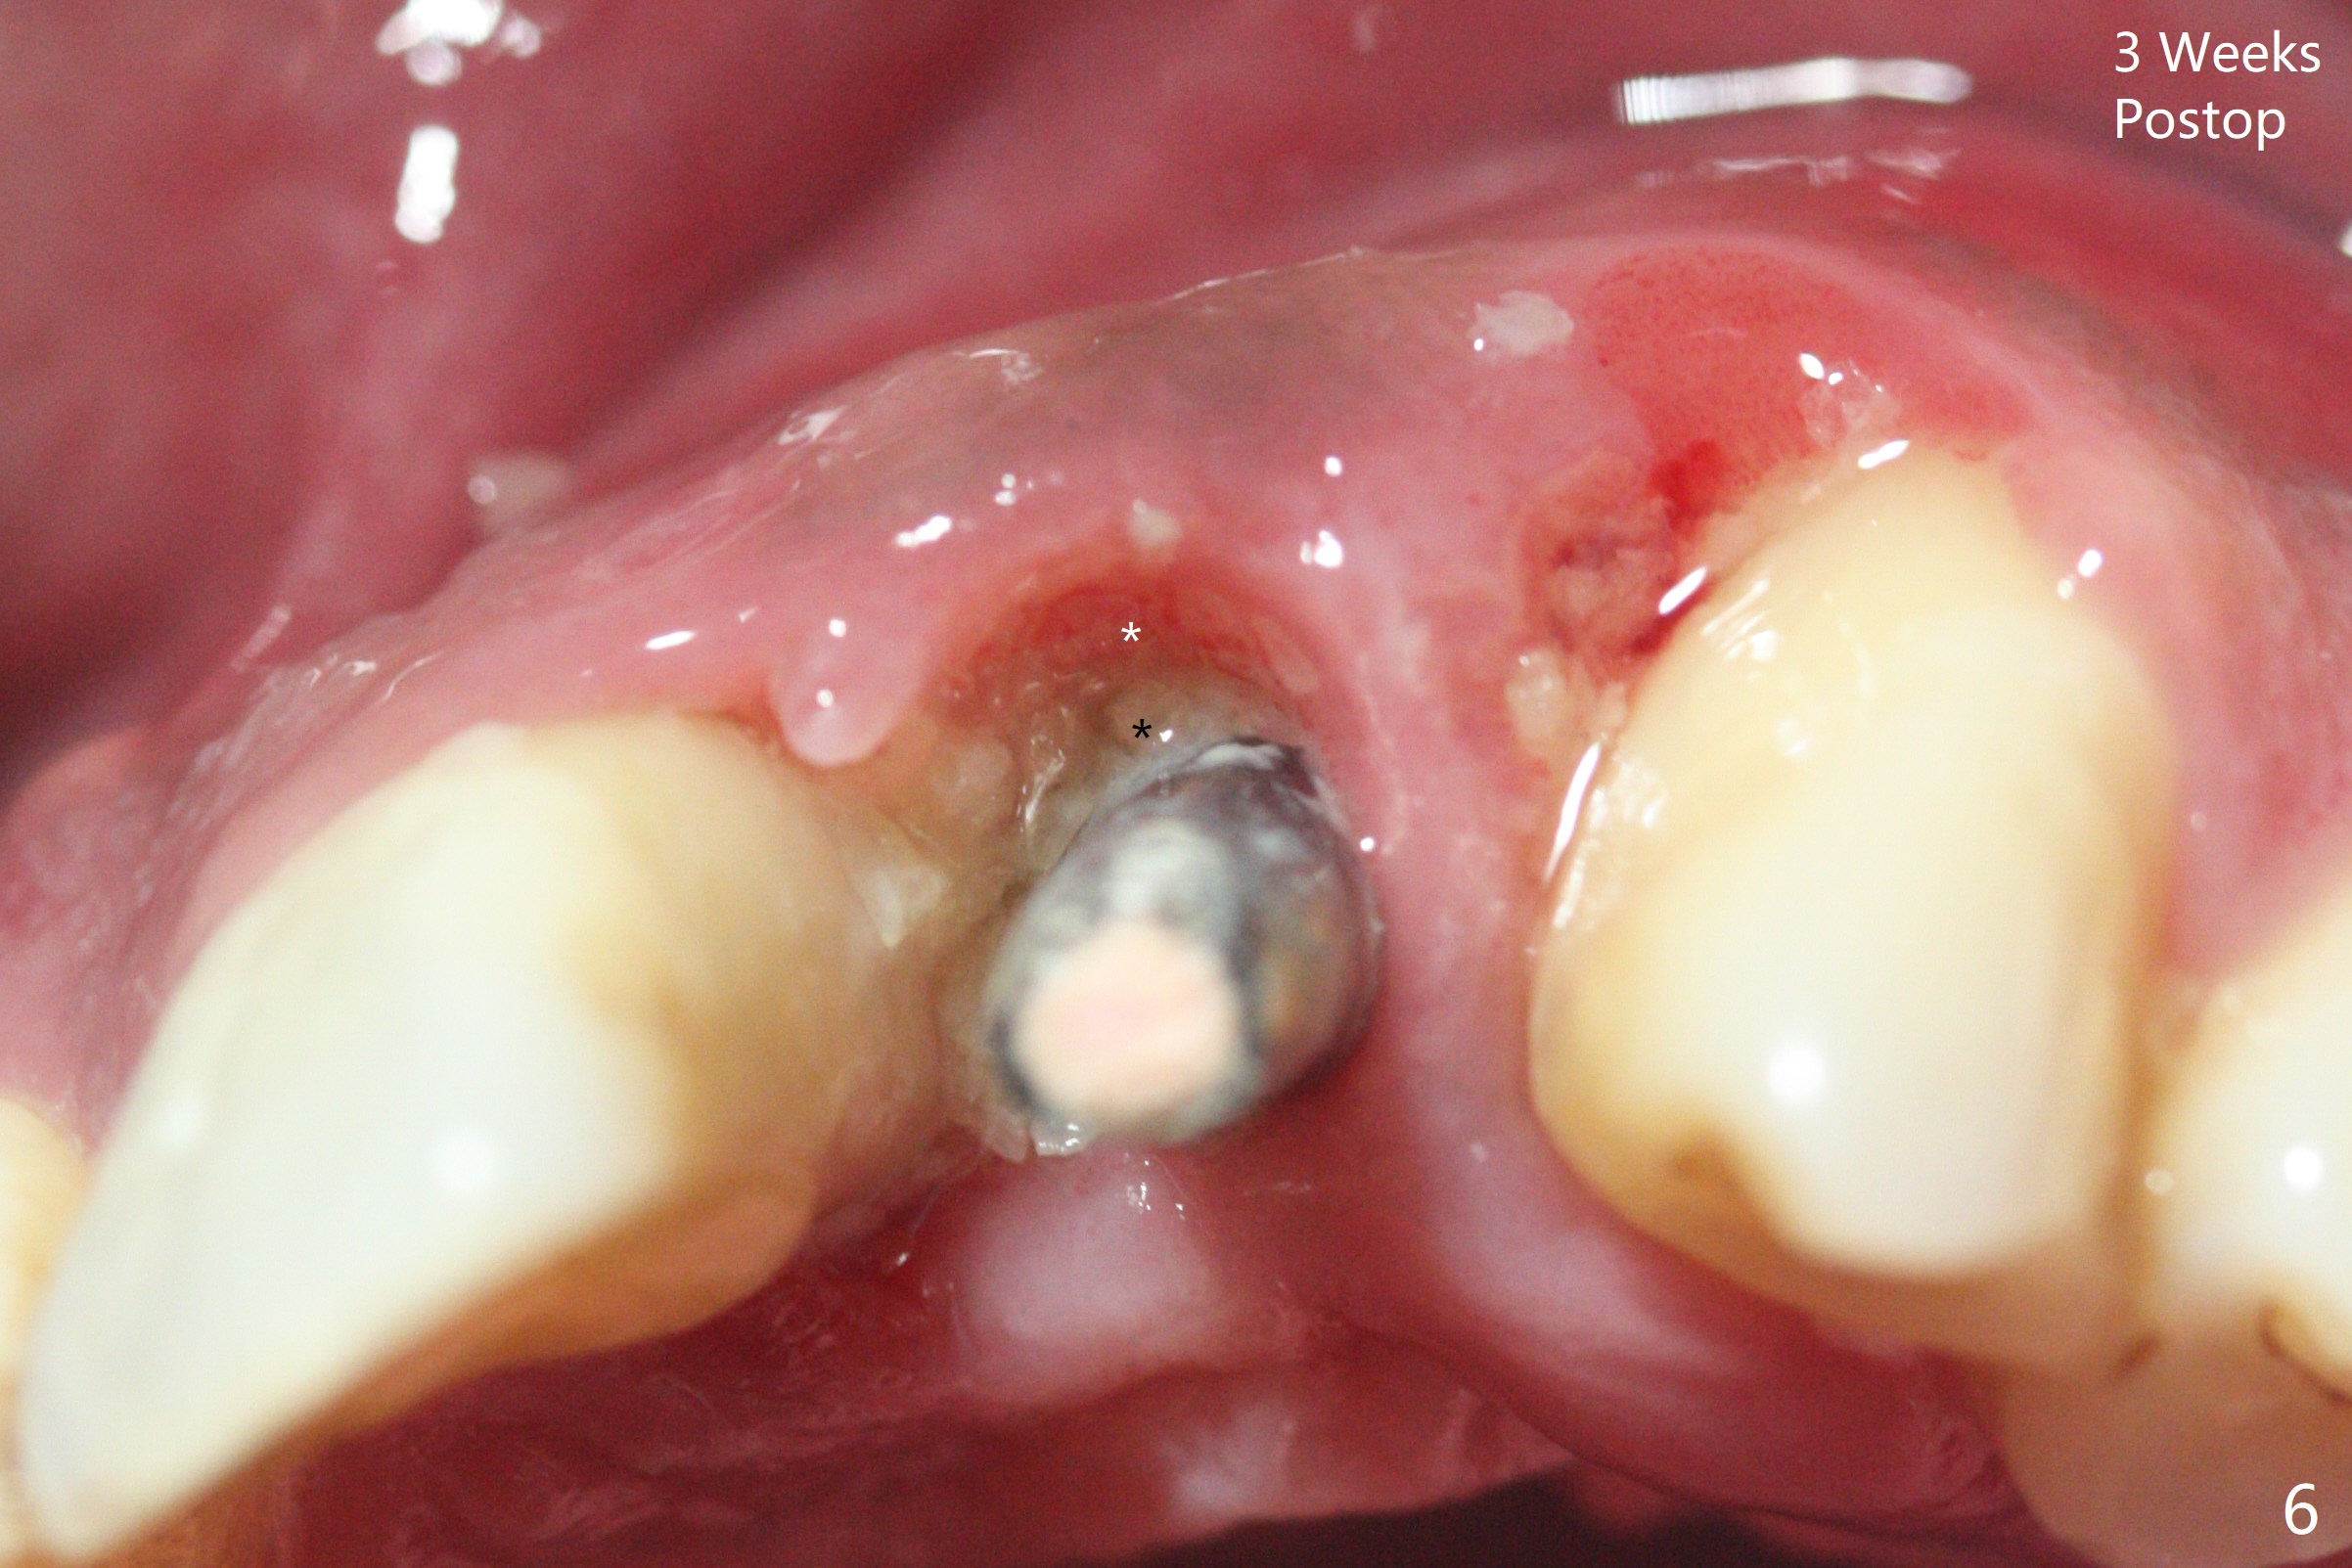

实验结果表明红管抽取上清液形成粘性骨块比白管快。左上二拔除,即刻徒手钻洞(图一),初步植入3.8x11.5毫米植体(图二),调整植体深度,然后放置直径4.5毫米长基台(图三,DIO UF; 牙龈厚度大于6毫米),最后填入大量粘性骨粉(图四,五 *),植体颊侧近中骨粉不足(图五 ^),之后再次充填骨粉。制作即刻修复物,颊侧瘘道和牙槽窝开口放置PRF膜。术后三周临时牙冠松动,取出后者,颊侧空间有两个区域:牙龈和骨粉(图六:白,黑星号)。由于脑部手术,术后接近一年病人回来取模。由于基台长,临时牙冠还没有脱落(图八)。牙龈袖正常(图九:*)。术后一年骨粉仍在植体,基台交界处(图十)。